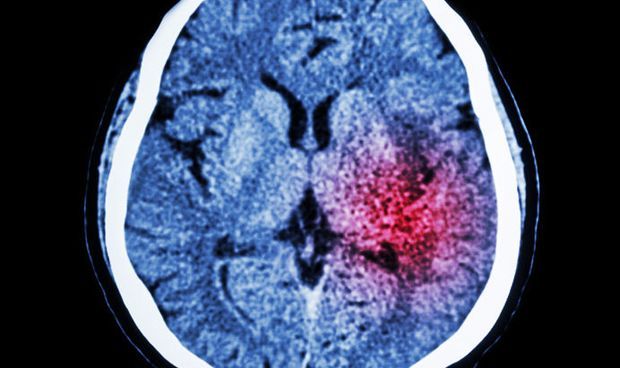

Un artículo publicado por el grupo de investigación de Jeff Meyer en 2018, del Centro para la Adicción y Salud Mental (CAMH) de Canadá, demuestra que una depresión de larga duración se vincula con inflamación y cambios estructurales del cerebro. Alteraciones similares también se pueden observar en enfermedades degenerativas, como Alzheimer y Parkinson.

El estudio consistió en analizar imágenes del cerebro midiendo la inflamación, utilizando la tomografía por emisión de positrones (PET). El estudio tiene en cuenta tanto la duración de la depresión como si el paciente estaba o no en tratamiento.

Los resultados demostraron que las personas con depresión de larga duración, con períodos sin tratamiento, tienen una inflamación cerebral

mayor que aquellas que sufren una depresión de corta duración. Igualmente, aquellos que habían sufrido depresión de más larga duración presentaron mayores cambios estructurales del cerebro.

La investigación, también, demostró que si la depresión se trata a medida que avanza se disminuye la inflamación y la alteración estructural del cerebro. Y recomiendan por ello, que hay que actuar de manera rápida frente a la depresión para evitar que todos estos cambios se produzcan a nivel cerebral.

En opinión del Dr. Carbonell, este artículo basado en neuroimagen demuestra, una vez más, la importancia de que se trate la depresión como una seria enfermedad. Precisa de identificarla lo antes posible para poder tratarla de manera rápida.

Imagen del cerebro. Extraída del estudio realizado por Jeff Meyer